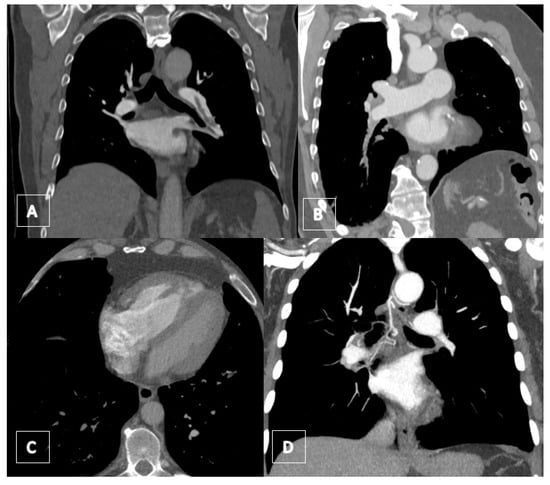

3.4. Computed Tomography Pulmonary Angiography (CTPA)